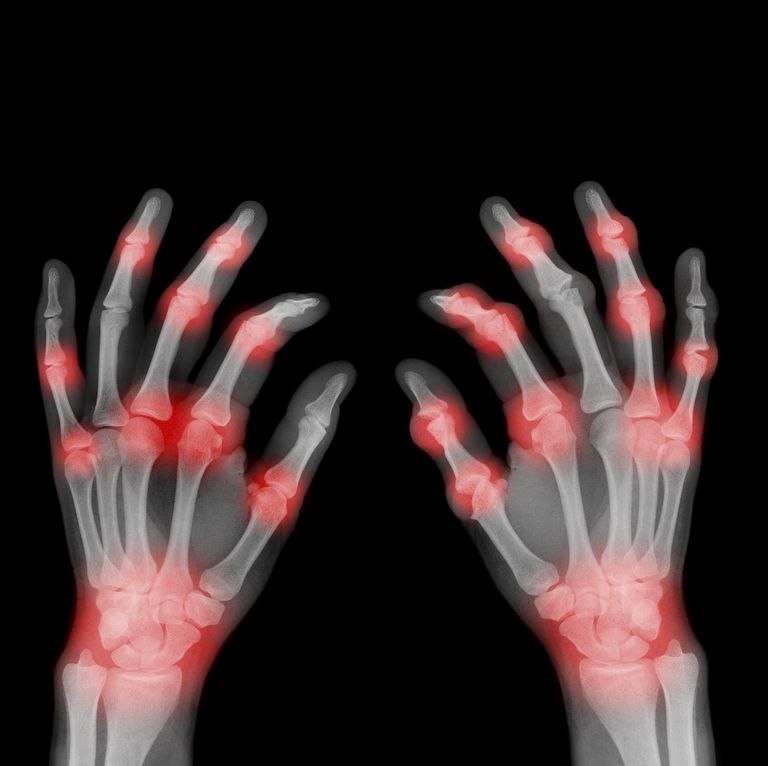

손가락 관절 통증 증상 손가락 관절 통증 증상엔 사물을 꽉 쥐었을때 마디마디가 콕콕 쑤시는 통증을 느끼신 분이라면 손가락 관절염을 의심해 봐야 합니다.

손가락 관절 통증은 심해 질수록 손가락이 강직이 되거나 손을 쥐었다 폈다 할 수도 없을 정도로 퉁퉁 붓습니다. 그리고 만성적인 손가락 관절염인 경우엔 손가락 관절에 변형까지 나타 날 수 있으니 미리 예방하시는 게 좋습니다.

손가락 관절 통증의 중요한 원인으로는 류마티스 관절염, 퇴행성 손가락 관절염 등이 있습니다.

류마티스 관절염, 퇴행성 관절염 손가락 관절 통증 치료약